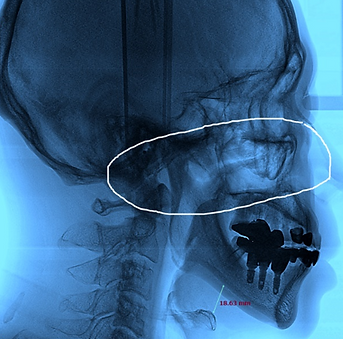

CIP INDEX, developed by Ilmi snoring and rhinitis research institute, is an index that calculates the relative occurrence probability

through structural and functional analysis of 15 factors that cause snoring sleep apnea using X-RAY and CT. By using CIP INDEX,

it is possible to increase the treatment success rate by not only identifying the cause and severity of the disease, but also quantifying

Airway width

before

after

Airway section

at the most narrowed